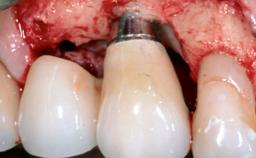

A 37-year-old male patient was referred to the Department of Periodontology at the University of Bern, Switzerland, by a private dentist. Tooth 21 had been lost due to trauma and had been replaced with an implant and a cemented single crown. The tapered-effect tissue-level implant had a diameter of 4.1 mm, a length of 12 mm, and a sandblasted and acid-etched (SLA) surface (Straumann Dental lmplant System; Institut Straumann AG, Basel, Switzerland). The metal-ceramic crown had been cemented permanently, leaving a submucosal gap between the implant shoulder and the crown margin. Absence of marginal bone loss apical to the polished transmucosal neck of the implant could be observed .